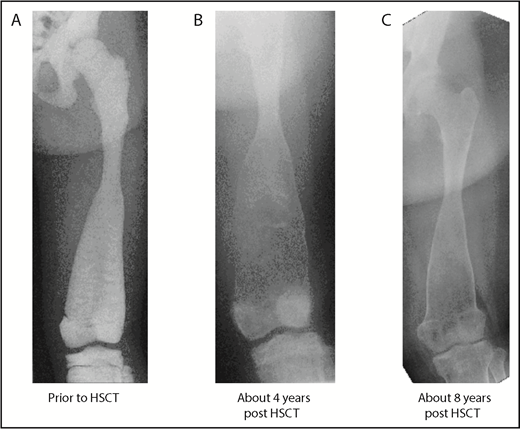

Baseline and follow-up plain radiography of the left lower extremity (femur) of patient 3. (A) Before HSCT, highly increased bone density with significantly diminished radiograph transparency, “ballooning,” especially of the distal femoral diaphysis, and meta/epiphysis. Transversal intraosseous dense horizontal lines are seen. (B) About 4 years after HSCT regression/normalization of bone density, however, decreased cortical lining and even increased osseous “ballooning” is seen. (C) About 8 years after HSCT, remodeling of bone size and complete normalization of cortical thickness is seen.

Pathological fractures are reported for 2 patients merely in the first year of follow-up. All surviving patients showed a significant improvement in their clinical condition and quality of life; in particular, their hematological abnormalities improved (no further need for transfusion of blood or platelets). They suffered no further deterioration in their vision or hearing. Bone density and bone deformation improved over months and years in all patients (Figure 1; supplemental Figure 3), and no further pathological fracture occurred from 1 year after transplantation. Osteomyelitis of the jaw in P2, P3, and P4 resolved (reconstruction of P3 in Figure 1; P3 in supplemental Figure 2). Two patients dependent on a wheelchair (P3, P4) are walking again without assistance (supplemental Video). All patients were able to attend school or to go to work.